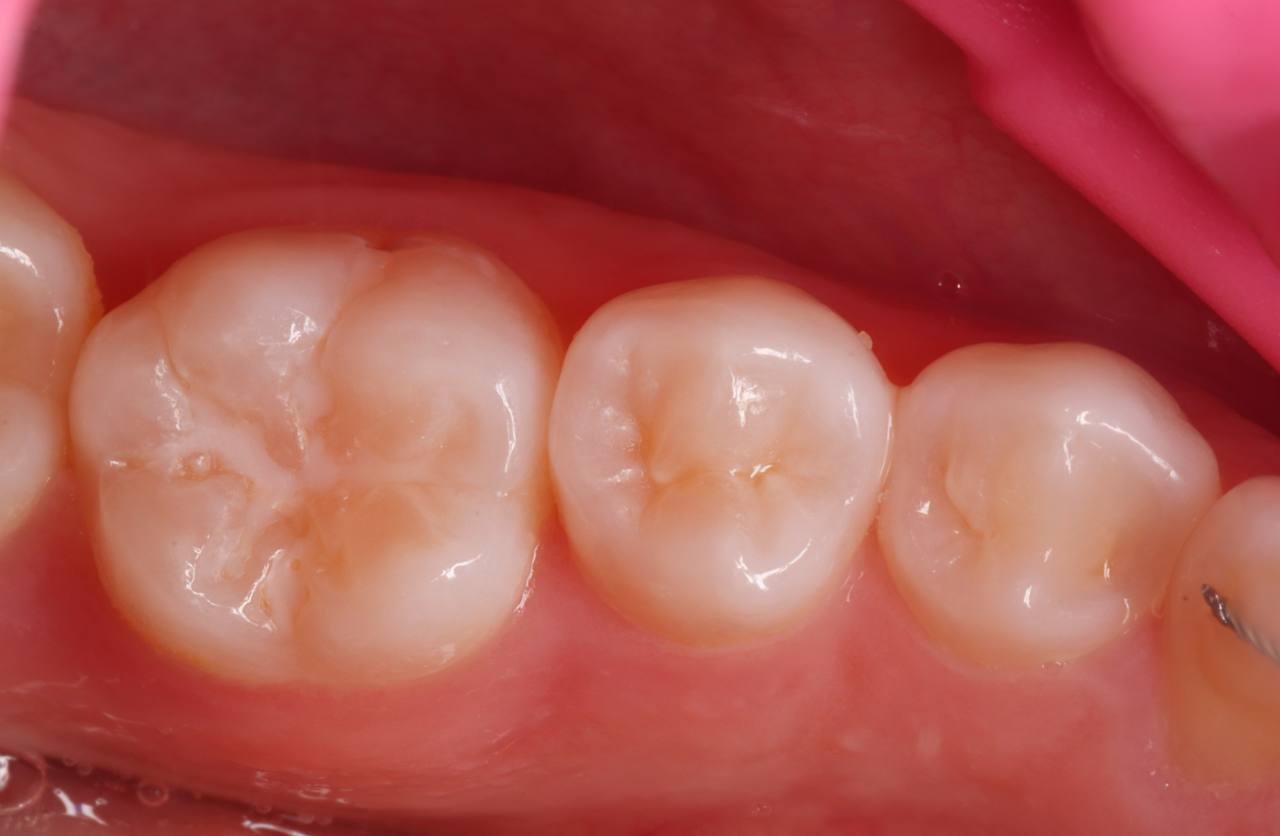

1. Pre-operative View of the Tooth (Image 1)